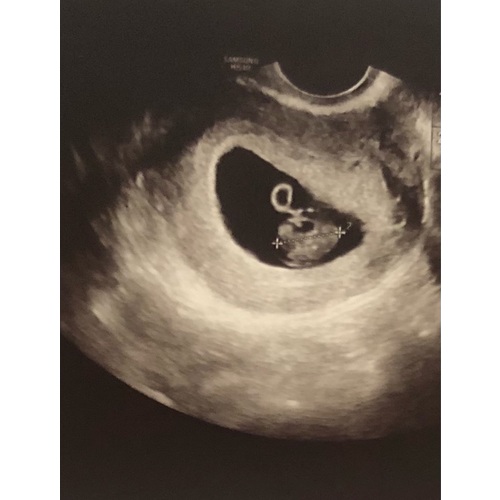

Volgens de Ramzi methode wordt er op deze manier voorspelt welk geslacht je krijgt.

Ligt je placenta aan de linkerkant van je lichaam?

Dan verwacht je waarschijnlijk: een meisje!

Bevindt je placenta zich aan de rechterkant van je lichaam?

Dan groeit er in je buik waarschijnlijk: een jongen!

Het is jammer dat je niet hebt gevraagd welke kant de placenta zit. Want het kan namelijk zijn dat de echo gespiegeld word weer gegeven.

Inwendige echo: Zie je op de uitdraai van een inwendige echo de lichte vlek rechts in de baarmoeder? Dan verwacht je volgens de Ramzi-theorie een jongen. Wanneer je hem links in de baarmoeder ziet, zou je van een meisje in verwachting zijn.

Uitwendige echo: Als de echo via je buik is gemaakt, is de echo gespiegeld. Zie je op de uitdraai van de echo de lichte vlek rechts? Dan zou dit betekenen dat je een meisje krijgt. Een lichte vlek aan de linkerkant wijst bij een uitwendige echo op een jongen.